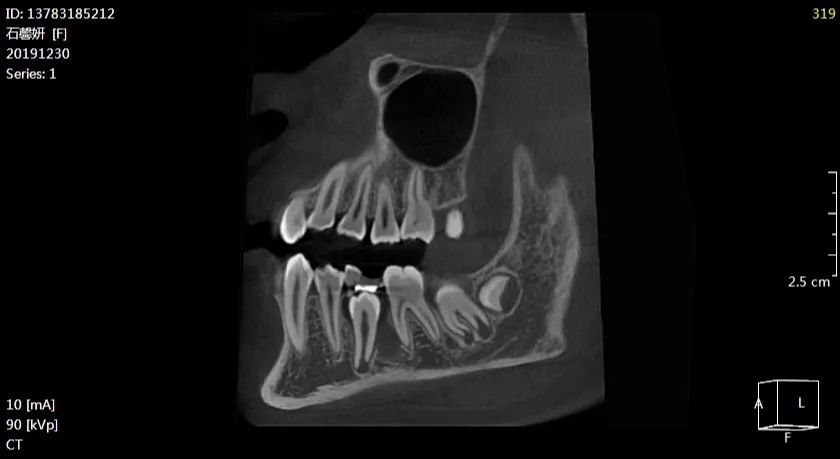

石xx201912303536颌骨囊肿ct137xxxx5212

图片尺寸840x459